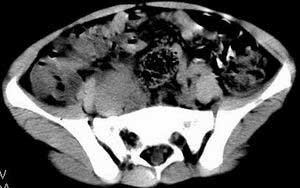

| 患者,男,9岁,因右下腹包块入院,血象不高,不规则发热,常超40度。 平扫: ![]() ![]() ![]() ![]() ![]() ![]() ![]() ![]() ![]() ![]() ![]() ![]() ![]() ![]() ![]() ![]() ![]() ![]() 增强: ![]() ![]() ![]() ![]() ![]() ![]() ![]() ![]() ![]() ![]() ![]() ![]() ![]() ![]() jiajie发言:骶椎右前区不规则软组织肿块,边缘光整,密度均匀,增强后均匀强化,右腹股沟区可见肿大淋巴结,临床有时发热,考虑淋巴瘤,儿童盆腔肿瘤应与神经母细胞瘤和横纹肌肉瘤鉴别。 longzhanghui发言:印象:盆腔右后壁不规则软组织肿块,并向前延伸.似为多个肿块融合,呈中等强化.初步考虑淋巴瘤. 听蝉观竹发言:右侧髂内、外组淋巴结肿大,从其形态和融合的情况看,同意大家意见-----考虑恶性病变,但是9岁男孩还要注意检查睾丸情况,有无隐睾? 常常类似情况是隐睾发生精原细胞瘤淋巴结转移,这个病例也要注意这一点!!! 广东凌发言:大家好,在这里我想说一下个人观点,我建议上传图片的同志能否辛苦一点就是把病史和图片都上传完整一点,比如这个病人的腹膜窗,并且这个病人的肠道的准备也是不怎么好,就从现有的质料看:病灶属于淋巴结肿大当无大的争议,有融合趋势,其内无坏死,边缘强化为主,故考虑:淋巴瘤!建议用腹膜窗看一下和肠道的关系! 阿圣发言:病灶属于淋巴结肿大当无大的争议,有融合趋势,其内无坏死,边缘强化为主,故考虑:淋巴瘤 结果是:淋巴瘤 病例来源:ct762。由宁静致远发布: http://www.radinet.com.cn/forum_view.asp?forum_id=4&view_id=2182 |